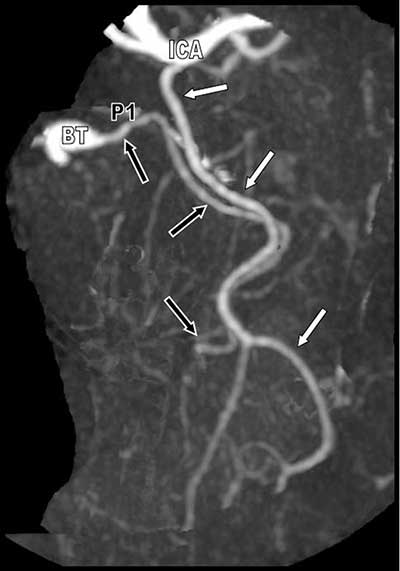

Figure 2

Selective oblique Maximal Intensity Projection (MIP) reformation of the duplicated left posterior cerebral arteries.